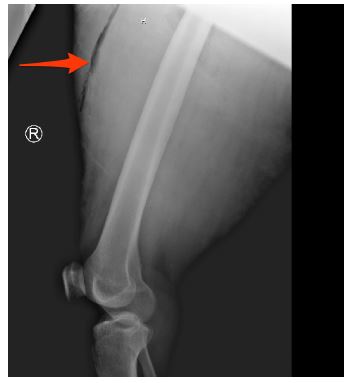

Plain film imaging of the right thigh was obtained to evaluate for any evidence of fracture or bony injury. The image (Figure 2) was notable for a radiolucent linear finding that was compatible with soft tissue gas; highly suggestive of an open soft tissue injury.

Figure 2: A plain film image of the right thigh. Red arrow denotes a linear area of radio-lucency indicating a traumatic separation of epidermis from deeper subcutaneous tissues.